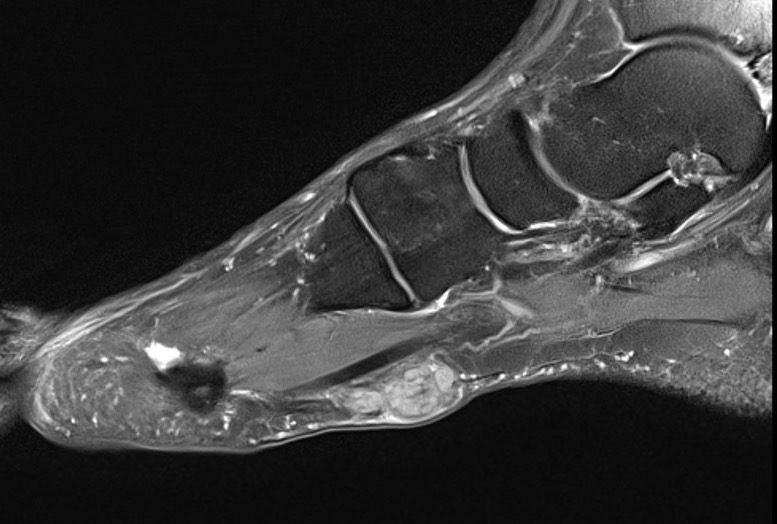

MRI

Focal oval shaped lesions within the plantar fascia

Usually affects medial and central bands of plantar fascia